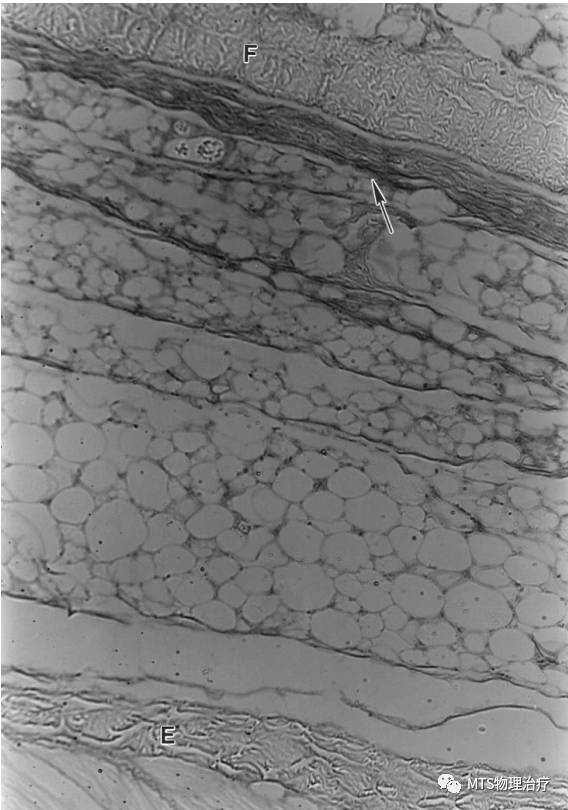

透明质酸在深筋膜深层或者肌表面存在,深筋膜在肌外膜和蜂窝组织间形成滑动界面。

在踝及腕部的支持带发现三层独特结构, 内层滑动层, 含透明质酸分泌细胞。